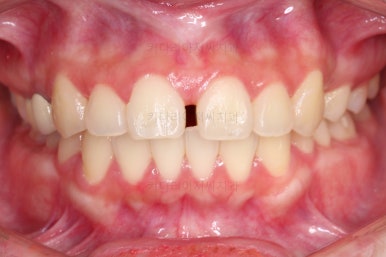

초진 시 얼굴모습인데요.

옆라인 예쁘고 입술을 다물었을 때 편안한 입술 느낌도 좋았어요.

다만 치아 사이 틈새가 벙러져 미적으로 좋지 못한 상황이었고요.